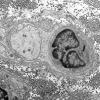

PERIPHERAL NEUROPATHY

6 AXONAL DEMYELINATION (BASIC PROCESS)